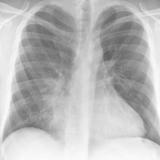

Case 2 PA

Date: 02/28/2004

Views: 3135